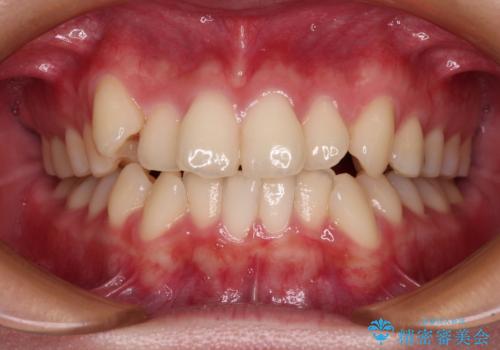

歯並びのせいで歯ブラシがしづらい マルチブラケットを用いた抜歯矯正

担当医 大元洋佑